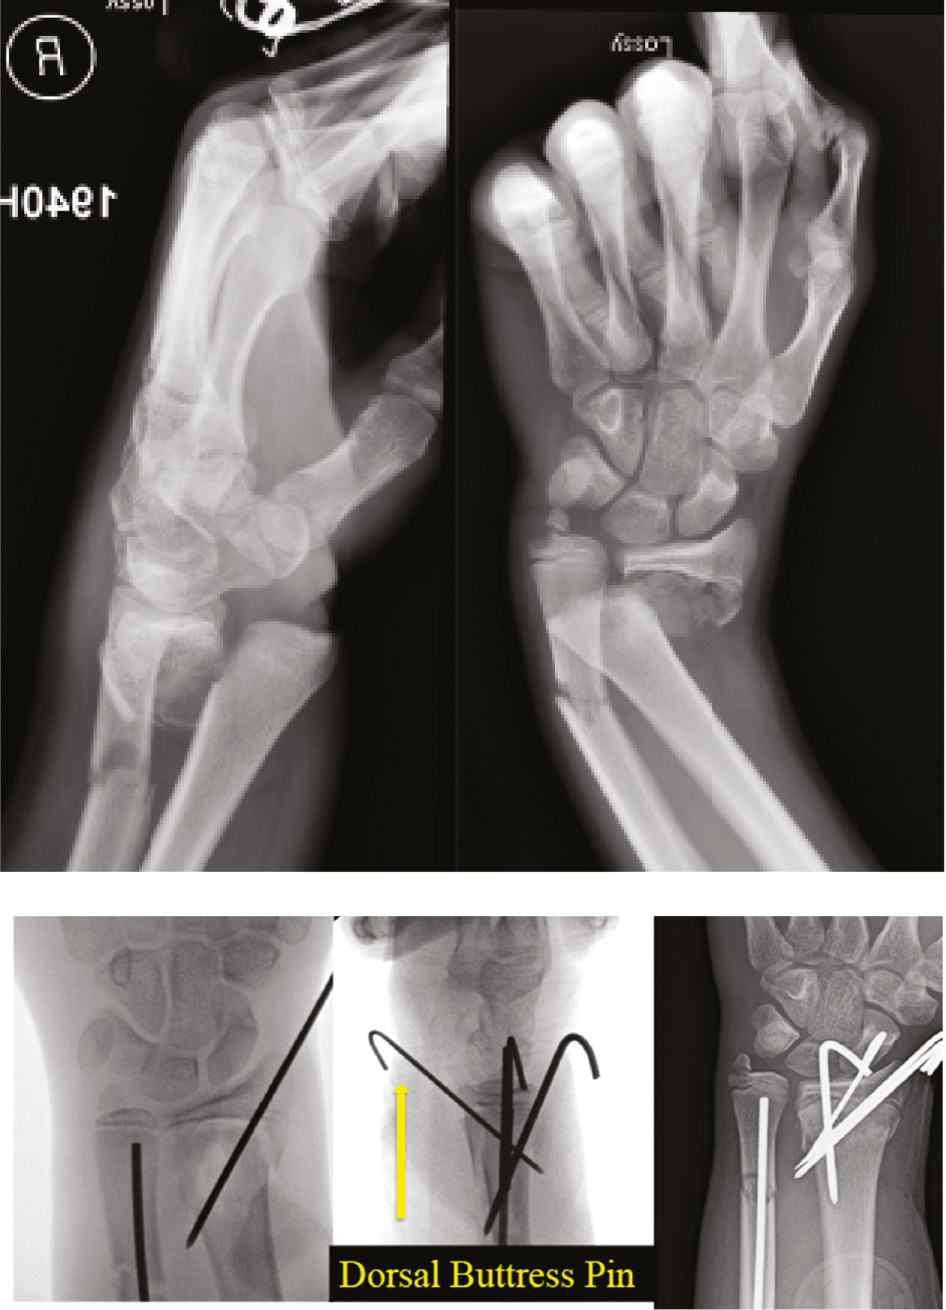

Pin fixation is considered for displaced fractures that cannot safely be stabilized with immobilization alone. Pins may be used both to effect reduction and to provide stabilization. For instance, the Kapandji technique describes the insertion of pins into fracture sites for the purpose of dislodging fragments and manipulating them into reduced positions. Ultimately, once a fracture is reduced, it can be stabilized percutaneously with smooth pins that are removed in clinic after initial healing. This technique was first described in pediatric distal radius fractures.3 Pins can be used in conjunction with casting to hold fractures out to length. The “pin-in-plaster” method was described as a blend of casting with percutaneous pinning and could be considered the original external fixator for the maintenance of reductions that would likely fail with plaster alone.5,6 Finally, pins can be modified and used for internal fixation (Figure 1).

Closed manipulation in the operating room followed by percutaneous placement of 1-2 1.6 mm K-wires traversing the fracture site is the classic method of pinning these injuries. The pins are placed from distal-to-proximal and radial-to-ulnar using an oscillating driver to minimize risk of injury to the superficial radial nerve. Placement of wires dorsally is also an option. The Kapandji technique has been shown to be effective in addressing distal radius fractures that are difficult to reduce. A K-wire is inserted between fracture fragments to lever the fracture to achieve reduction while a different K-wire or two are placed to secure fixation; alternatively, reduction may be performed with a Freer elevator in this way.52,53 (Figure 12)

Figure 12. A 14-year-old snowboarder with displaced comminuted distal radius and ulna fractures. The comminuted radius required several pins, including a dorsal buttress pin that while not crossing the fracture, is a block to displacement.